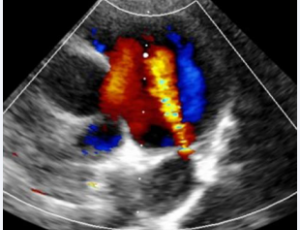

April 18, 2025 Case Report

Abstract Transcatheter patent ductus arteriosus (PDA) closure is a device-based technique for correcting PDA. In general, an isolated PDA is easier to close, but conditions such as a smaller PDA, PDA spasm, or a dilated main pulmonary trunk make device closur..... -